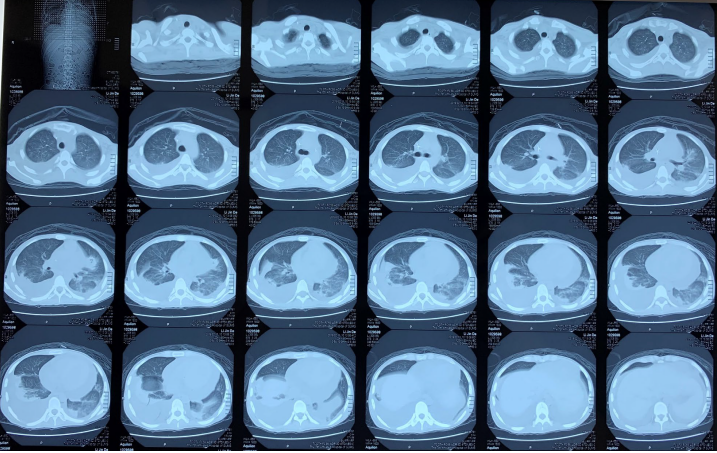

1所示为患者在中山大学附属第七医院住院期间胸部CT的变化情况。入院第3天(2018年12月26日)时,患者胸部CT表现为双侧胸腔积液,肺部少许感染,以及大量心包积液。2019年1月7日双肺出现较前明显增多的模糊密度增高影,考虑肺泡出血可能大。经过一系列治疗,2019年2月11日复查的胸部CT(图1右下角,图2)可见肺部多发斑片状渗出性和实变病灶有明显吸收好转,但左肺上叶舌段、右肺中叶外侧段、下叶斑片病灶较前增大或新增。

1  患者外院住院期间胸部CT变化情况

图片

2  患者胸部CT(2019年2月11)